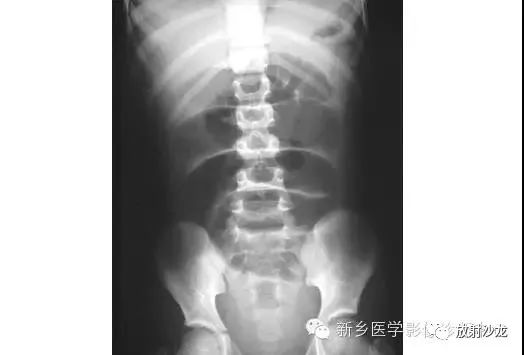

上图为9岁,腹痛、呕吐患儿所做的腹部平片。该患儿有阑尾炎合并腹膜炎病史。影像学异常是什么,最有可能的病因是什么?腹部X线片显示小肠襻的明显扩张、环状襞的消失,这与小肠梗阻的诊断相一致。该患儿既往有腹膜炎病史,梗阻是由腹腔粘连造成的。这个孩子最终经保守治疗康复。